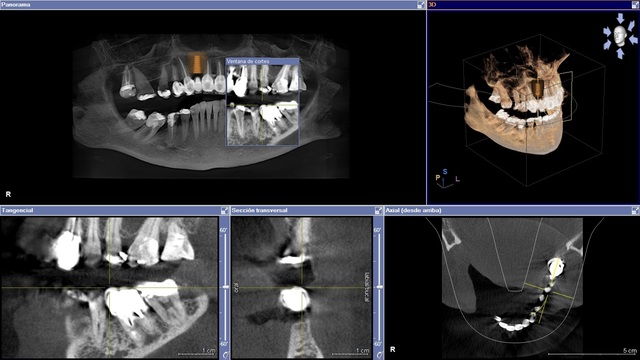

• Primer radiografía dental.

Primer radiografía dental.

Obtenida por W. G. Worton, utilizando cráneos humanos desecados.